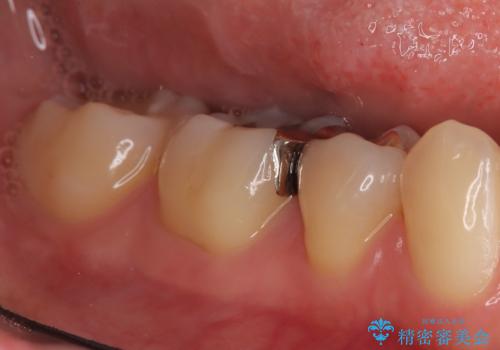

- 「銀歯を白しくしたい」を主訴に来院された患者さんです。

銀歯を外し、虫歯を除去した後にハイブリッドインレーで治療を行いました。